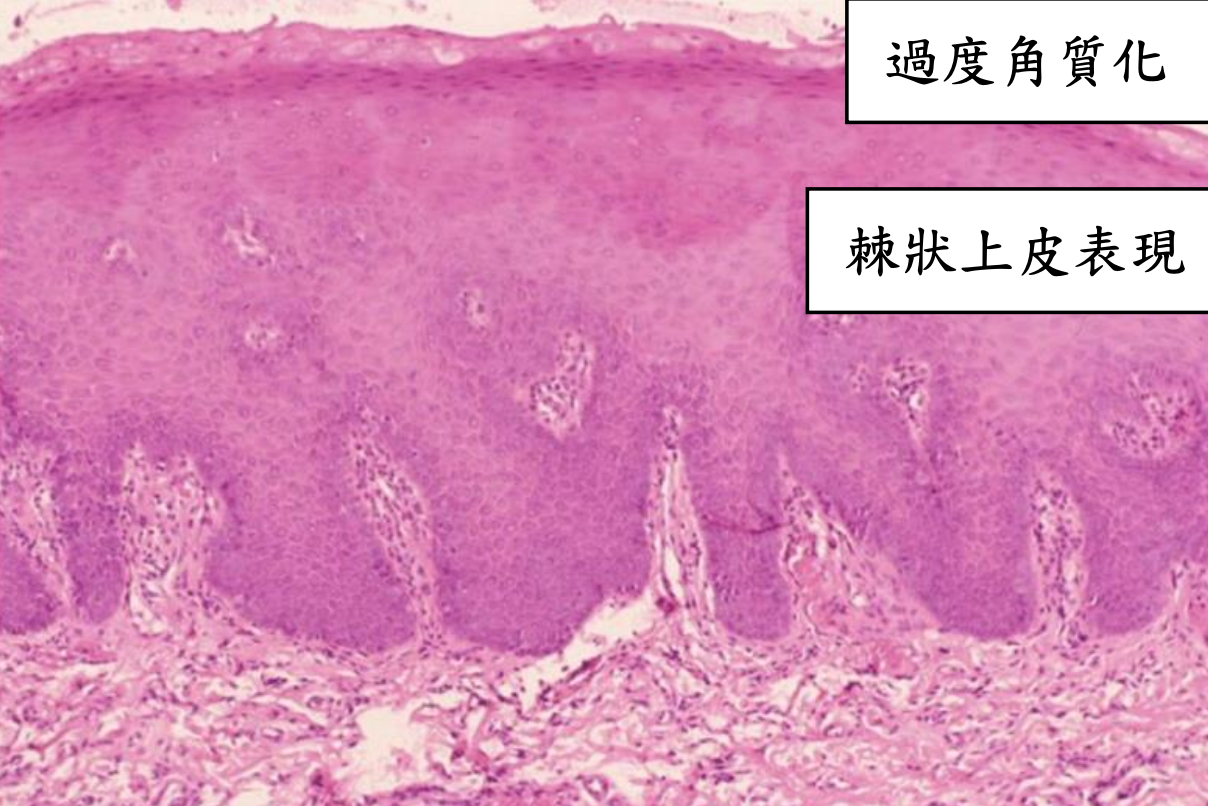

| stratified squamous epi. 包結締組織 hyperparakeratosis (有核、顆粒層缺失)  |

Papillomatous variant

根據和正常上皮的相似度及產生的 keratin 多寡來分級

- Grade I, well-differentiated: 產生正常量的 keratin

- Grade II, moderately-differentiated: 產生少量的 keratin

- Grade III, poorly-differentiated: 幾乎不產生 keratin